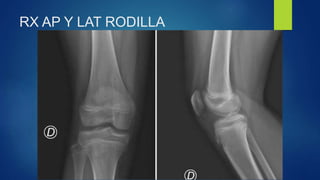

PRUEBA VENTAJAS DESVENTAJAS

RX

Rápido, muy disponible, barato Radiación, no hay signos agudos

RX AP Y LAT RODILLA